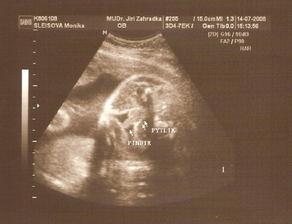

14.7. 3D utz - nádherný zážitek. i když mrňousek moc nespolupracoval a pořád se schovával. Navíc je v plodovce asi dost šupinek mázku, tak jsou fotečky neostré. I tak to bylo krásný. A podle statistik máme termín 12.10. 😲